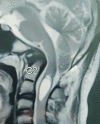

A variety of factors could contribute to facial oedema during a prone neurosurgical procedure. For optimal surgical exposure, suboccipital cranial surgeries frequently necessitate extreme neck flexion. Extreme neck flexion in the prone position can impair venous drainage of the facial and oropharyngeal structures, leading to life-threatening oedema, so a two-fingerbreadth space between the chin and the sternum is critical. We present a case of massive facial oedema with submandibular swelling in a patient who underwent foramen magnum decompression in the prone position for Arnold Chiari malformation.